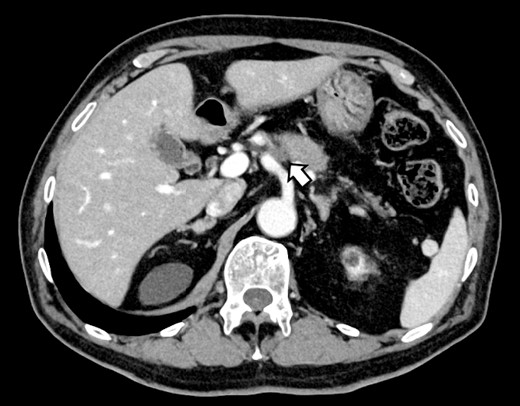

A 76-year-old man underwent DP-CAR after eight courses of gemcitabine and nab-paclitaxel therapy as preoperative chemotherapy for pancreatic body cancer with celiac artery invasion (Fig. 1). As the celiac axis had not invaded into the bifurcation of the left gastric artery, a modified DP-CAR (left gastric-preserving) was performed. Although post operative pancreatic fistula (POPF) developed on postoperative Day (POD) 5, and biliary fistula developed on POD 17. Bile leak was thought to be caused by the rupture of the choledochal duct due to bile duct ischemia caused by CHA transection. Subsequently, both the POPF and biliary fistulae were drained and fistulated. However, on POD 47, the drainage fluid became bloody. Contrast-enhanced computed tomography (CeCT) revealed a pseudoaneurysm at the junction of the gastroduodenal artery (GDA) and proper hepatic artery (PHA) (Fig. 2A and B).

Computed tomography after preoperative chemotherapy showing tumor invasion on the left side of the celiac artery.

(A, B) CT on postoperative day 48. Contrast-enhanced CT showing a pseudoaneurysm at junction of the GDA and PHA (arrow).